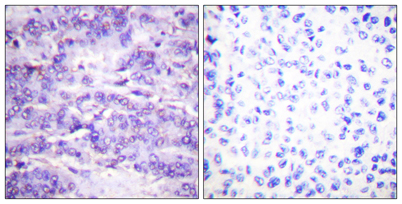

Immunohistochemistry analysis of paraffin-embedded human breast carcinoma, using MDM2 (Phospho-Ser166) Antibody. The picture on the right is blocked with the phospho peptide.

Immunohistochemistry analysis of paraffin-embedded human breast carcinoma, using MDM2 (Phospho-Ser166) Antibody. The picture on the right is blocked with the phospho peptide.